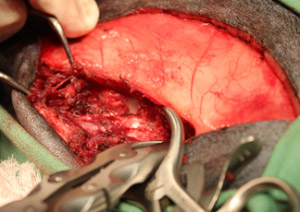

- まず背側の棘突起に沿って切開、多裂筋を分離し、関節突起を露出し、関節突起を除去後、片側椎弓板をラウンドバーにてバーリングし造窓しました。

- ケリソンパンチにて頭側尾側に造窓の拡張を行いました。